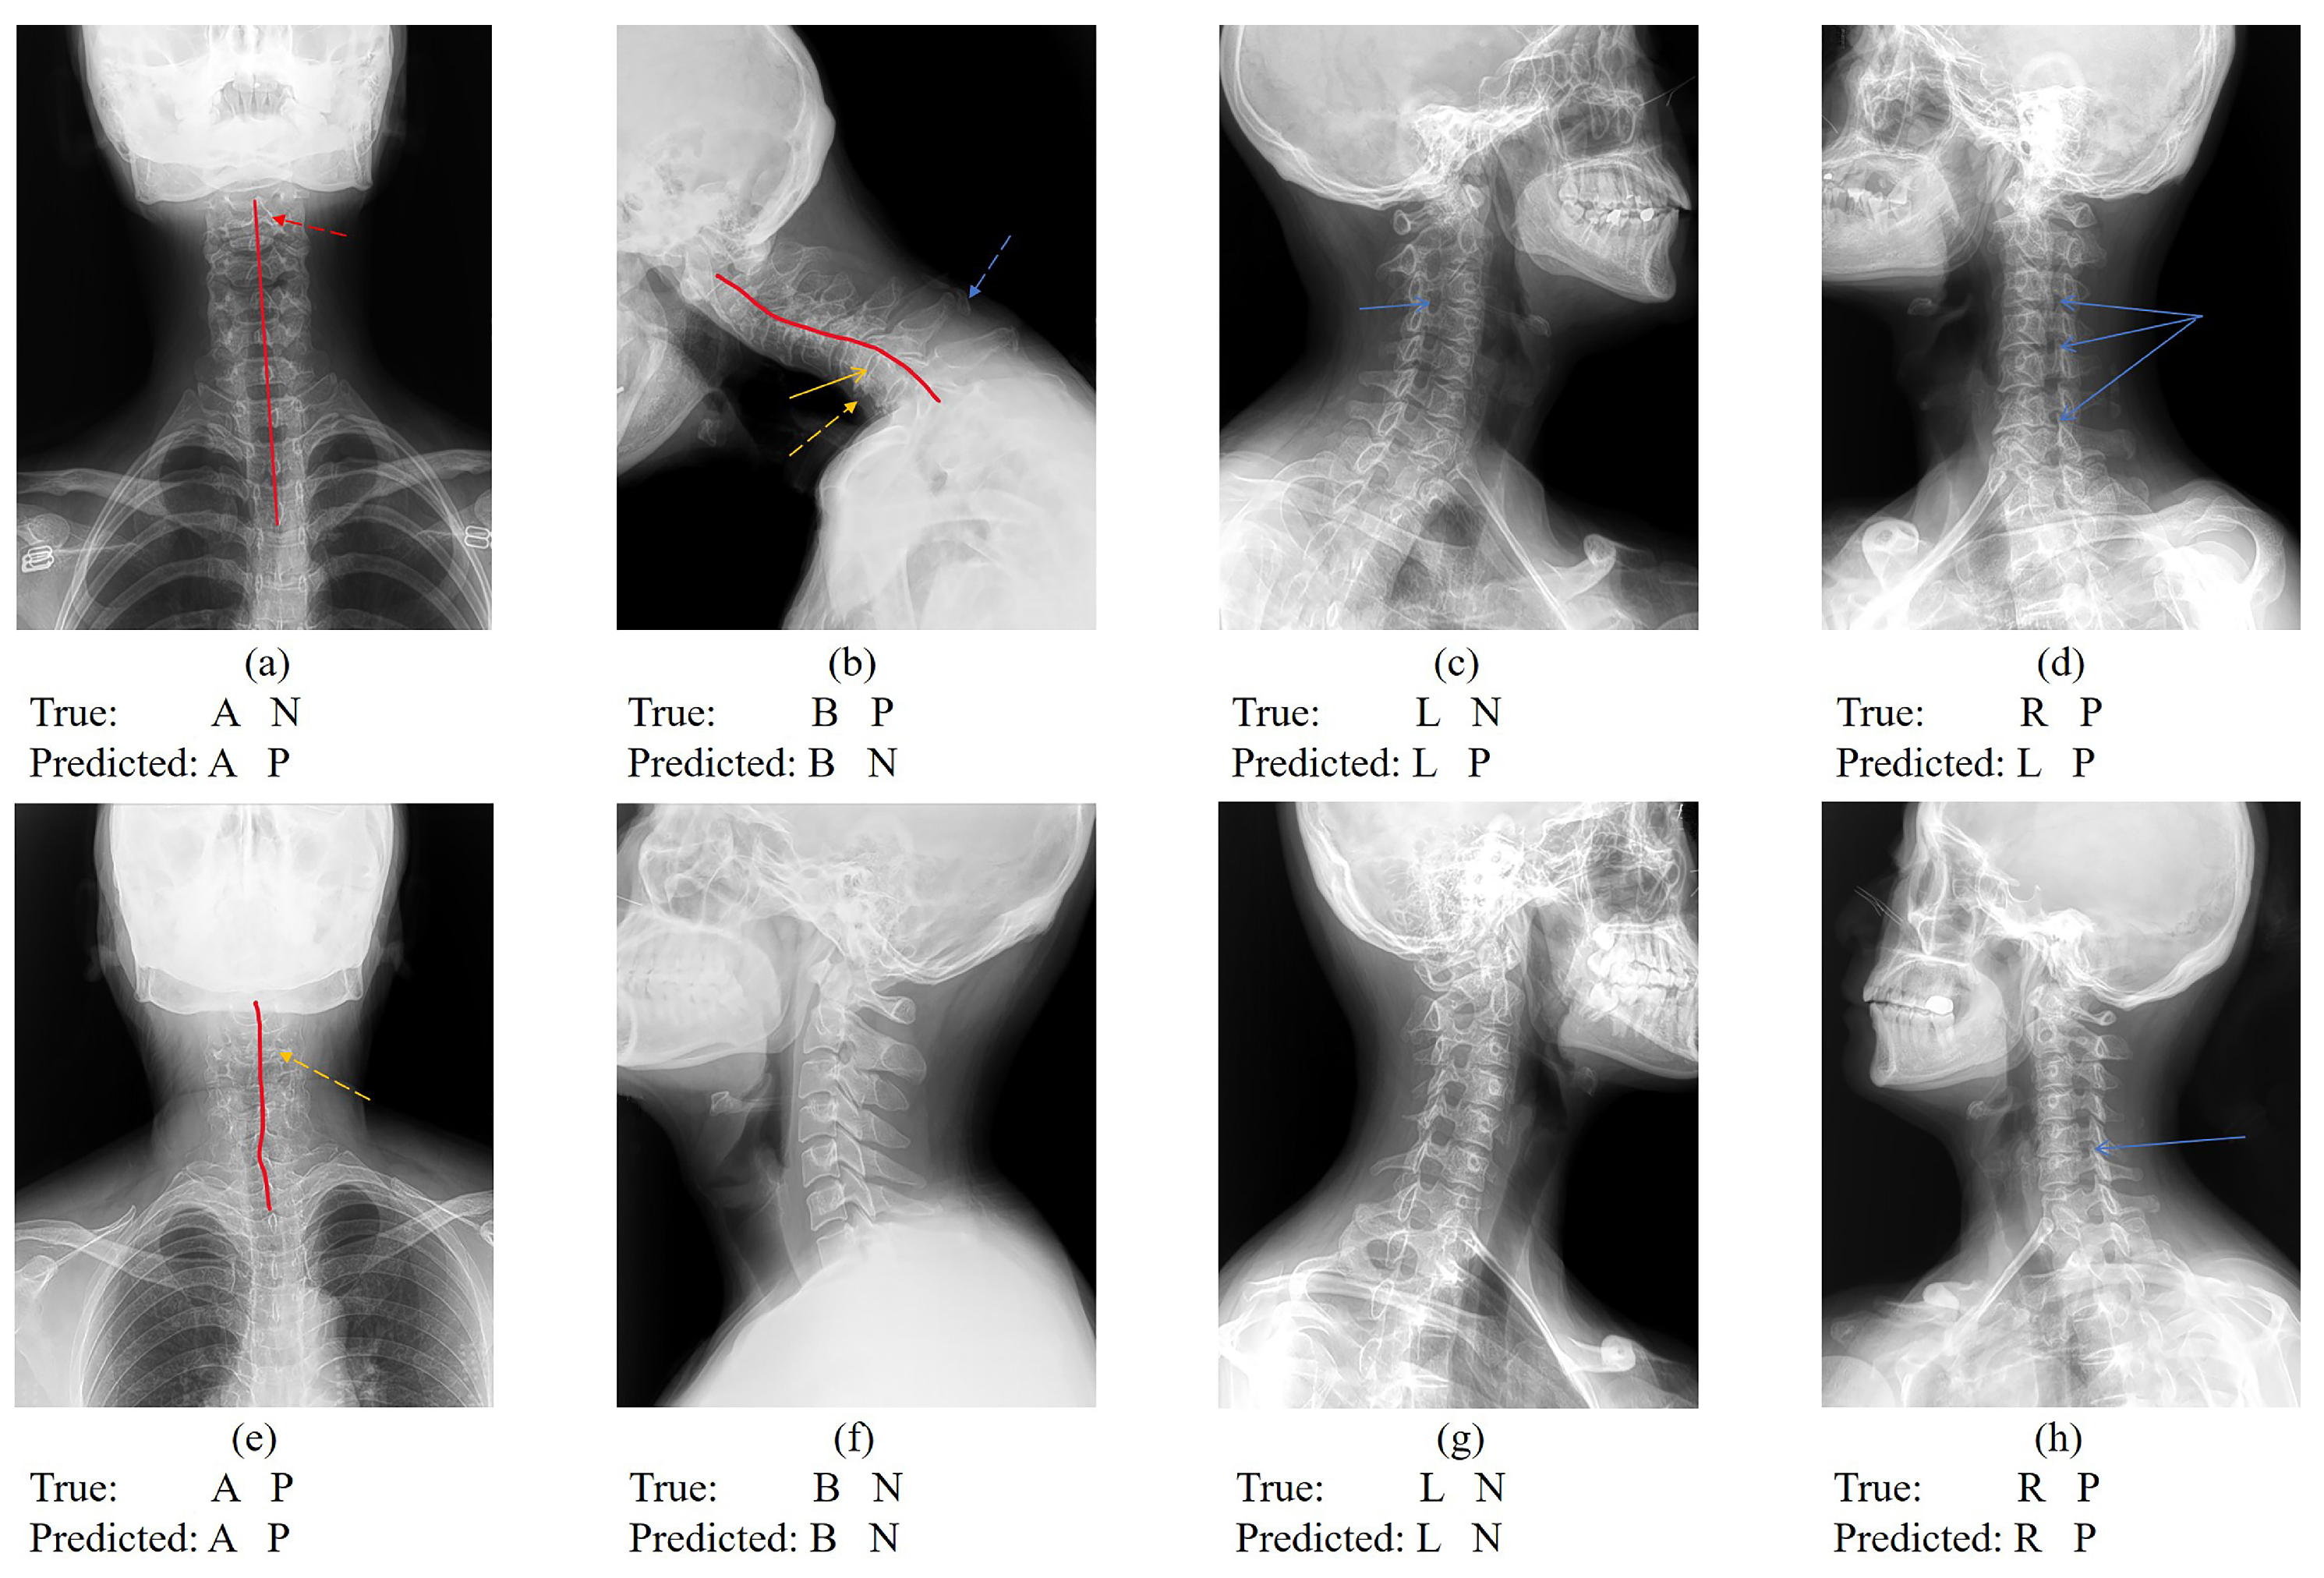

Despite the model’s exceptional performance in accuracy, sensitivity, precision, and F1-score, opportunities for enhancement remain. Notably, this retrospective study did not utilize standardized cervical spine imaging projection patterns. Variabilities such as hardware differences across devices, individual disparities resulting from X-ray imaging parameters (e.g., X-ray intensity, irradiation distance, and X-ray incidence angle), subjective imaging diagnostic criteria, and variations in patient positions complicate data processing (Figure 6). To mitigate overfitting associated with complex data, a novel model-processing method was employed. Parameters were saved not after every 100 training cycles but from the training sessions that exhibited the best performance within each set of 100 cycles. This approach, by minimizing the overfitting’s impact on model parameters, improved the model’s accuracy by 1.5% compared to traditional methods.

Figure 6. Cervical vertebra X-ray projection position classification and CS classification results. Figure (ac) represent that the cervical spine position is correctly classified but CS is incorrectly classified. Figure (d) represents that the cervical spine position is classified incorrectly but CS is correctly classified. Figure (eh) represent images with correct cervical vertebra position classification and CS classification. (“N” indicates CS is negative; “P” indicates CS is positive; the red line indicates the physiological curvature of the cervical spine; the red dotted arrow indicates the hyoid bone blocking the cervical vertebrae. the yellow arrow indicates the intervertebral space; the yellow dotted arrow indicates osteophyte formation; the blue dotted arrow indicates ligament calcification; and the blue arrow indicates the intervertebral foramen).